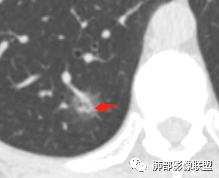

晨读:中老年女性,体检来诊。右肺下叶后基底段近胸膜下mGGN,其内实性成分似见毛刺及分叶,并见空泡征,周围GGO边界清楚,近肺门端见血管影伸入病灶并略显扩张,病变与支气管关系观察欠佳。多考虑恶性,腺癌可能性大。鉴于首次检查,常规建议抗炎治疗后复查,观察病灶变化情况,再决定下一步诊疗方向。

病灶内低密度像扩张的支气管,整体被病灶包围,可以定为空泡,PC没有这么大的牵拉,曲霉的话病变范围太小,而且是体检发现。病灶周围磨玻璃似清非清,病灶下缘磨玻璃是明确清晰的,因此诊断倾向于粘液腺癌,比较心虚的地方是没有抗炎复查。

右肺下叶基底段胸膜下小结节,周围模糊晕征,其内光滑囊腔影,考虑小空洞,其内血管走形自然,周围软毛刺,常规考虑炎性结节,隐球可能性大,建议抗感染后复查,鉴别粘液腺癌。

连续层面显示这个应该是空泡,或者小空洞,远端没有,近端也没有,周围环形软组织增厚。而空泡,影像上只是根据5mm界线,病理上不一定。

假如这是含气支气管,伴随的哪条动脉呢?近端从哪来?为啥环形壁增厚而又不均匀?都不太符合,所以支持空泡或小空洞。

上次刘纯老师提出,空泡征是一个影像征象,不是一个病理征象,我比较支持,他就是一个影像上的小低密度腔,原因很多,但是影像上与小的空洞表现区分不了。其中的原理:有一条是内容物排出后的残腔,其实也是空洞的原理。

空泡征指结节内直径<5mm的气体密度影或低密度影,可单个或多个,且相邻2个以 上层面不能见到低密度点状影。